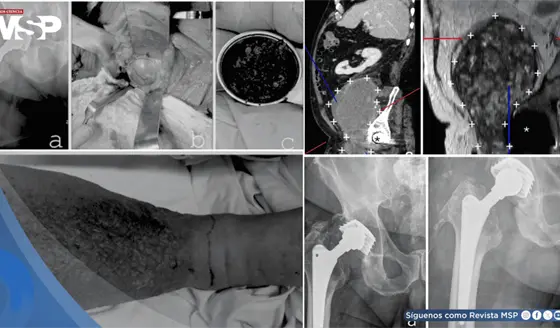

Uso de la pirotecnia